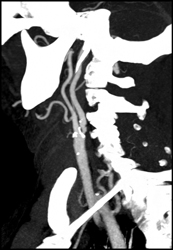

Carotid Artery Stenosis